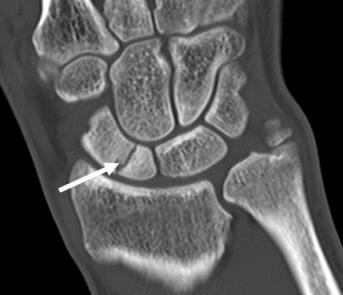

Chụp CT

Là phương thức tốt nhất để đánh giá vị trí gãy xương, góc, sự di lệch, kích thước mảnh gãy, mức độ xẹp và tiến triển của tình trạng không liền xương hoặc liền xương sau phẫu thuật

Đánh giá sự di lệch của gãy xương thuyền rất quan trọng để điều trị và thường được đánh giá tốt nhất bằng chụp cắt lớp vi tính (CT) lát mỏng (1 mm).

Sự di lệch được định nghĩa là:

- khoảng hở lớn hơn 1 mm,

- góc thuyền nguyệt ở phim nghiêng lớn hơn 60 độ,

- góc quay nguyệt phim nghiêng lớn hơn 15 độ hoặc

- góc trong xương thuyền (intra scaphoid angle) lớn hơn 35 độ.